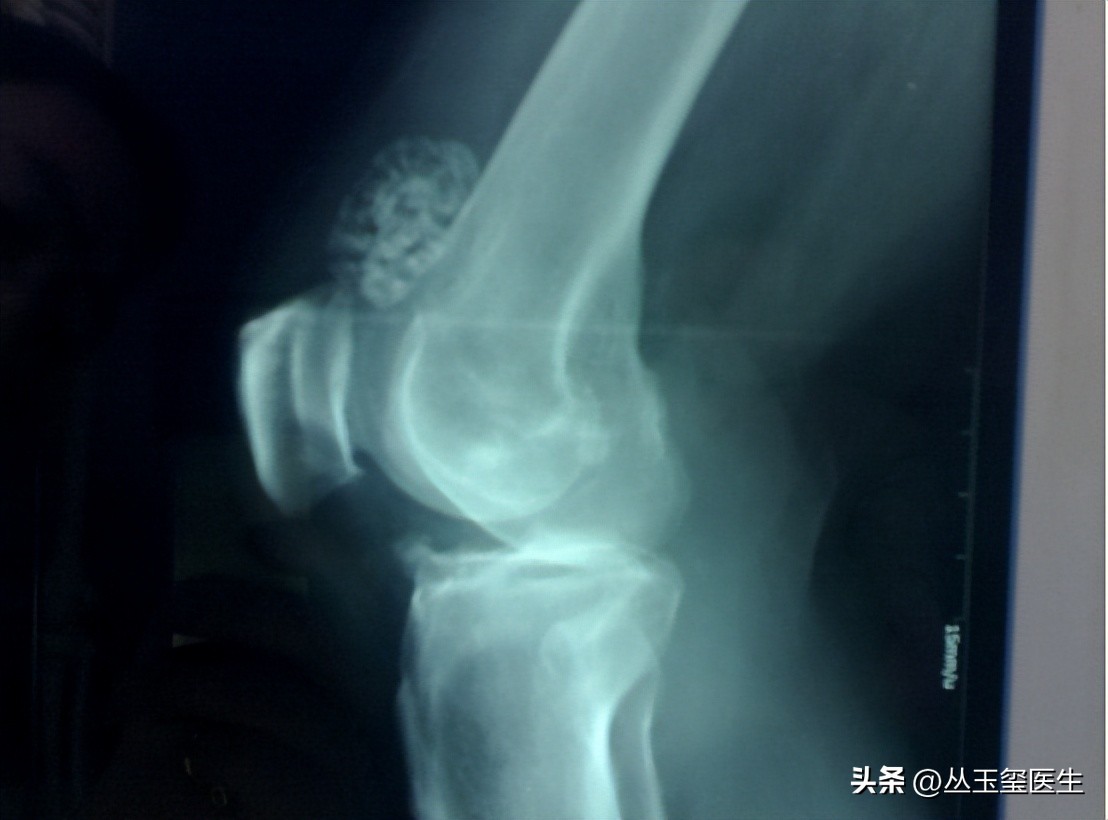

软骨瘤大多长在髓腔内,并且这种肿瘤大多不会单独出现,而是多个软骨瘤同时存在,随着软骨瘤的增长,身体会出现畸形的情况。

如果软骨瘤长在手指、脚趾或是四肢关节部位的话问题并不严重。

但如果软骨瘤生长在盆骨、胸部的话,就有可能发展为恶性,从而对其它器官造成影响,出现软骨瘤后,一般有以下两种症状。

一是出现肿块或红肿,一般软骨瘤都没有什么症状,但会明显的感觉到出现骨性肿块的情况。

如果我们发现身体局部出现肿块、质地坚硬并且按压后有疼痛感觉的话,就有可能是出现了软骨瘤。

二是关节疼痛,软骨瘤的发展很有可能会压迫神经组织,导致关节或是身体某个部位出现疼痛。

到了夜间时这种疼痛的症状会更加明显,这就需要我们到医院检查是否软骨瘤早期。